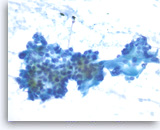

Acinar cell carcinoma,

Pancreas FNA, Cell Block.

The tumor cells form a prominent cribriform growth pattern with a deceptively bland and uniform appearance. A prominent cribriform pattern would be unusual for a low grade neuroendocrine neoplasm but immunohistochemistry is required to make the distinction. (Courtesy of Dr. Andrew Fischer)

10X

Acinar cell carcinoma,

Pancreas FNA, Cell Block.

The tumor cells form a prominent cribriform growth pattern with a deceptively bland and uniform appearance. A prominent cribriform pattern would be unusual for a low grade neuroendocrine neoplasm but immunohistochemistry is required to make the distinction. (Courtesy of Dr. Andrew Fischer)

10X